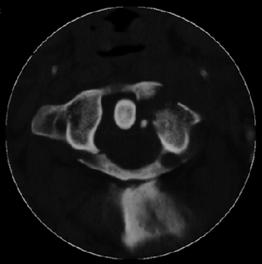

Fractura

Jefferson

Fractura Jefferson Fragmente

osoase la stanga apofizei odontoide

![]()

Fractura Jefferson Fractura spanzuratului

Aspect CT